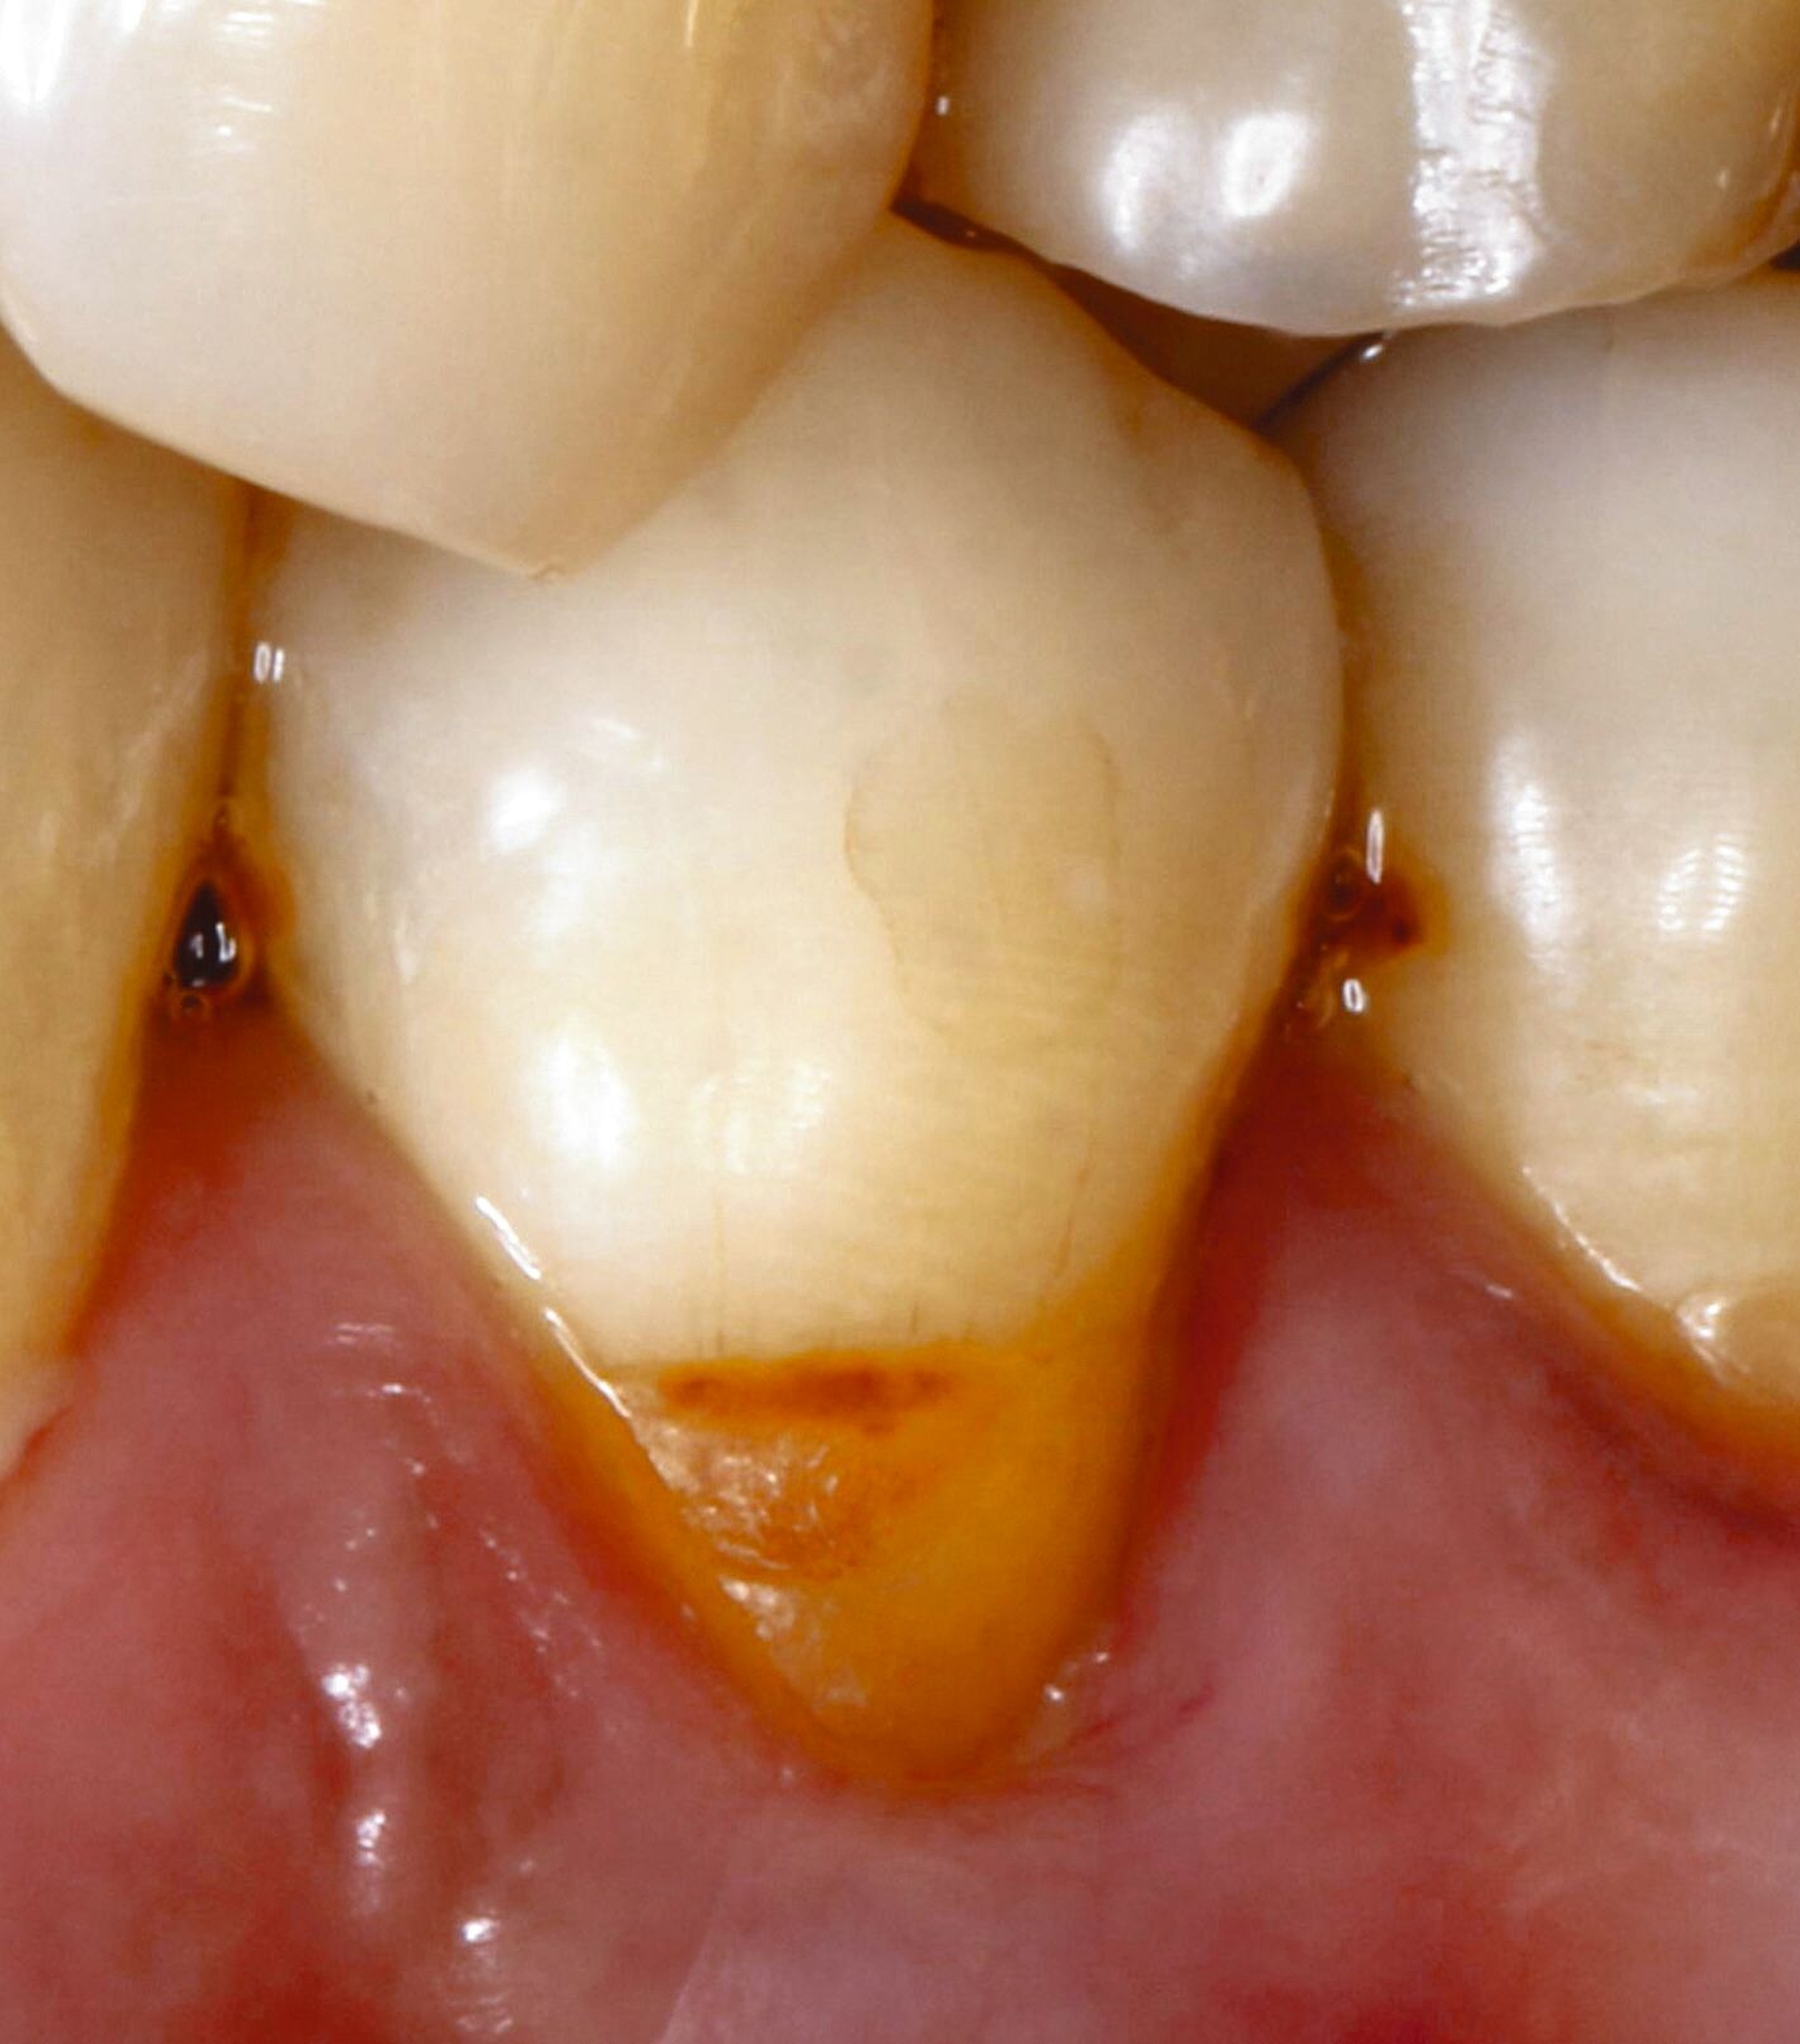

Wurzelkaries kann alle Bereiche der Wurzeloberfläche betreffen und ist in der Regel an Plaqueretentionstellen etwa im Bereich des Gingivarandes, der Kronenränder, der Einziehungen der Wurzeloberfläche oder des Interdentalraums lokalisiert. Zur klinischen Diagnostik sollte zunächst Plaque möglichst vollständig entfernt werden, um interdentale Bereiche einsehen und aussagefähig sondieren zu können. Während die Oral- und die Vestibulärflächen relativ einfach zu befunden sind, sollten die Interdentalräume unter guter Trockenlegung und Ausleuchtung beurteilt werden. Bei ausgedehnten Rezessionen ist die Diagnostik auch interdental gut möglich (Abbildung 4).

Für die Therapieentscheidung ist es essenziell, zwischen aktiven und inaktiven Läsionen zu unterscheiden (Abbildung 6). Die Farbe der Läsion ist zwar kein verlässliches Diagnosekriterium, aktive Wurzelkaries hat aber eher eine gelbliche oder hellbraune Farbe, ist in der Regel von Plaque bedeckt und fühlt sich bei mäßigem Sondieren weich oder ledrig an. Solche Läsionen bedürfen einer Intervention. Inaktive oder arretierte Läsionen haben in der Regel eine dunklere Farbe, sind meist plaquefrei und fühlen sich bei Sondieren hart an. Inaktive Wurzelkaries braucht keine weitere Intervention, auch wenn sie kavitiert, aber reinigungsfähig ist. Die Patientinnen und Patienten sollten jedoch über solche Befunde aufgeklärt werden.

Der Zugang zu approximalen Läsionen sollte, wenn immer möglich, von interdental versucht werden (beispielsweise im Fall von Abbildung 4). Wenn dies nicht möglich ist, erfolgt die Präparation von koronal, was jedoch oftmals erhebliche Opfer gesunder Zahnhartsubstanz erfordert. Die Versorgung der resultierenden tiefen approximalen Bereiche ist oftmals herausfordernd, zu den Behandlungstechniken sei auf die entsprechende Literatur verwiesen (beispielsweise [Muscholl, 2022]).